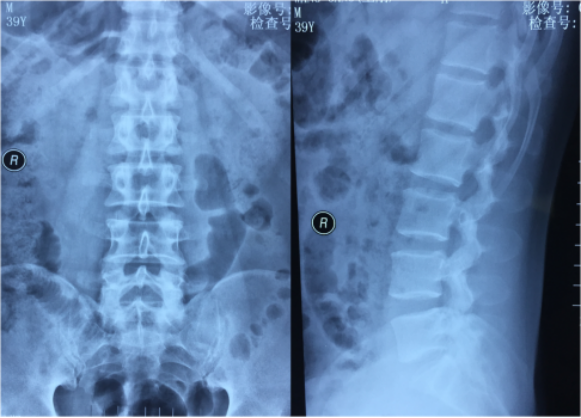

一例腰5骶一间盘脱出症脊柱内镜微创治疗病例

腰5/骶1椎间盘突出症 马尾神经损伤 后路减压融合内固定术病例

磁共振提示腰5骶1后外侧突出,骶1神经根受压

神经根明显受压术前mri提示:l5/s1椎间盘突出